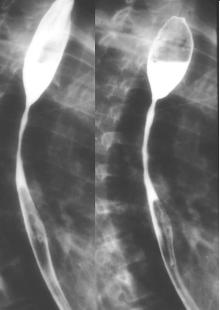

Nombreux de

grande ulcere avec image de extravation de contrast

baryte a exterieure et en longitudinale de oesophage

. . Image TOGD de oesophage . |

Image de

oesophagite a CMV situe 1/3 inferieure de oesophage

avex image des ulceres profondes de oesophage (

fleche blanche ) |